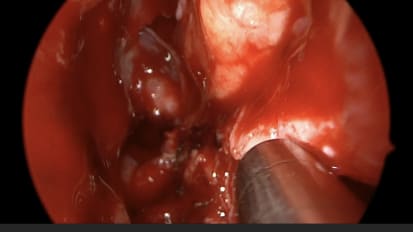

Mount Sinai head and neck surgeons perform a direct laryngoscopy with biopsy of the tongue base to confirm a diagnosis of squamous cell carcinomaMount Sinai Otolaryngology Surgical Series: Ear Drum Repair (Tympanoplasty) With Lateral Graft

Mount Sinai neurotologists perform a minimally invasive endoscopic approach to perform a lateral graft tympanoplastyMount Sinai Otolaryngology Surgical Series: Ear Tube Placement (Myringotomy)